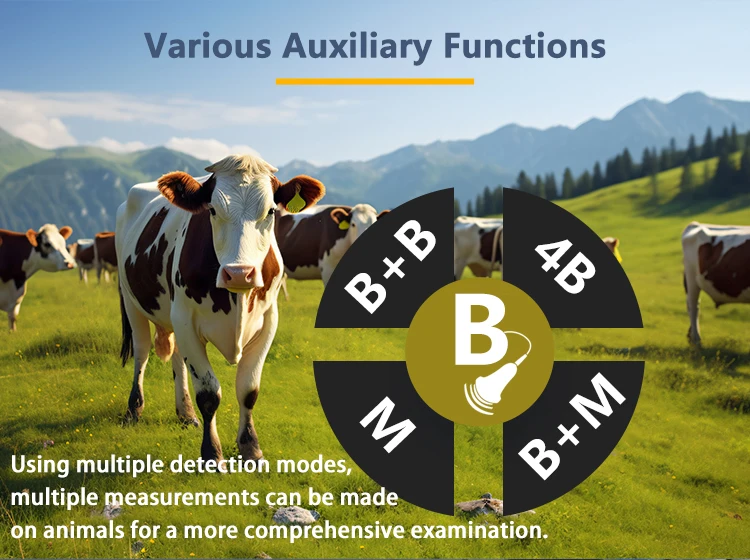

-Display mode: B,BM

-Display mode: B, B/M